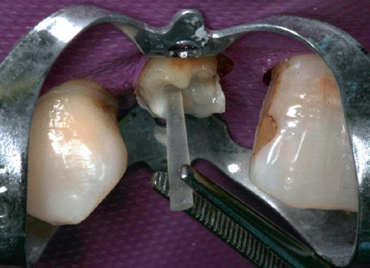

Das Bulkfill-Komposit SDR flow+, die Polymerisationslampe Smart- Lite Focus und die Core&Post Solution sind Teil des Behandlungskonzeptes R2C, das den Gesamterfolg endodontisch-restaurativer Behandlung in den Blick nimmt. Es bietet alle notwendigen Komponenten für eine durchgängig qualitativ hochwertige und sichere Behandlung von der Wurzel bis zur Krone: angefangen bei der Planung des endodontischen Eingriffs (3D Endo Software), der Eröffnung der Zugangskavität (Cavity Access Set), der Aufbereitung des Wurzelkanals (WaveOne Gold oder ProTaper Next) über die eventuell erforderliche temporäre Einlage (AH Temp) und Obturation (AH Plus, GuttaCore, Thermafil) hin zur Gestaltung der Kontaktpunkte (Palodent V3) der adhäsiven Füllung (Prime&Bond active, SDR flow+, ceram.x universal) bzw. zum Stift-Stumpfaufbau (Core&Post Solution) mit anschließender indirekter Versorgung (Aquasil Ultra+ und Celtra Press beziehungsweise CEREC und Celtra Duo). Das Behandlungskonzept R2C dient der Praxis als Leitfaden auf dem Weg zu einer lege artis endodontischrestaurativen Versorgung.